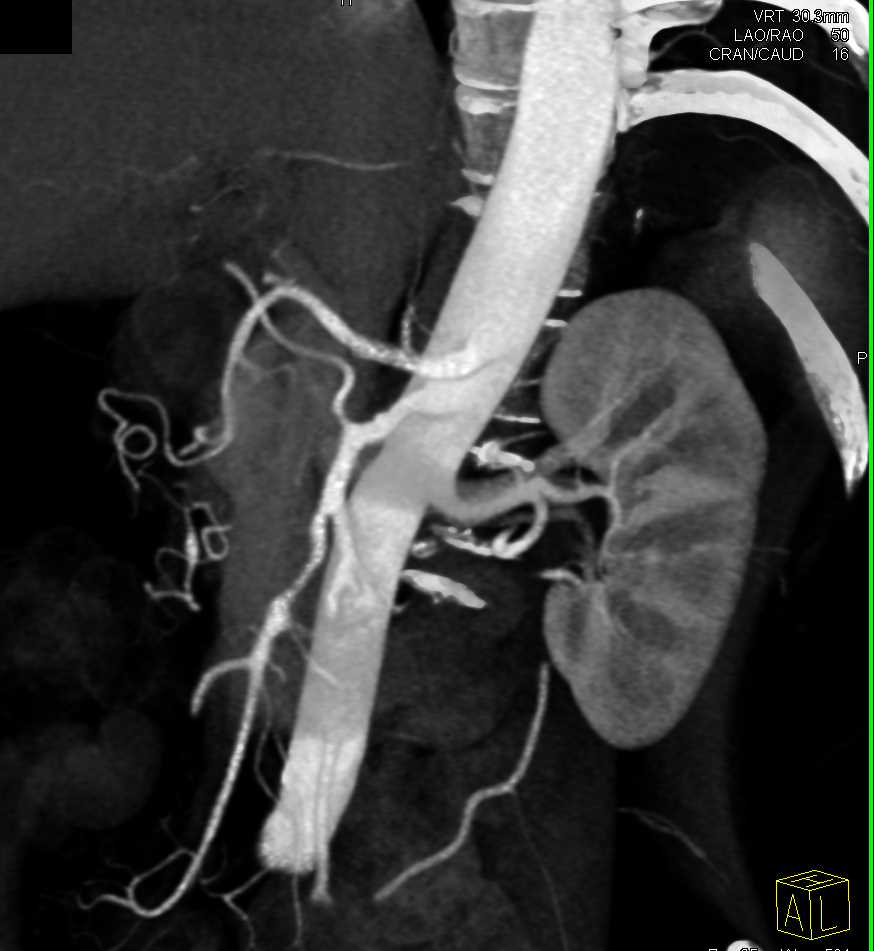

Subtle Neuroendocrine Tumor Body of Pancreas